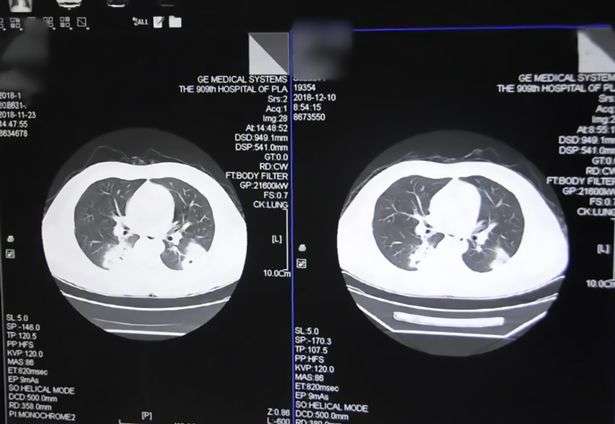

Saat diperiksa dan dilakukan X-ray, barulah terungkap bahwa Peng mengalami infeksi paru-paru yang parah.

Dari pemeriksaan lanjutan terdapat sebuah fakta yang mengagetkan, infeksinya itu ternyata disebabkan oleh bakteri yang biasa di temukan di alas kaki.